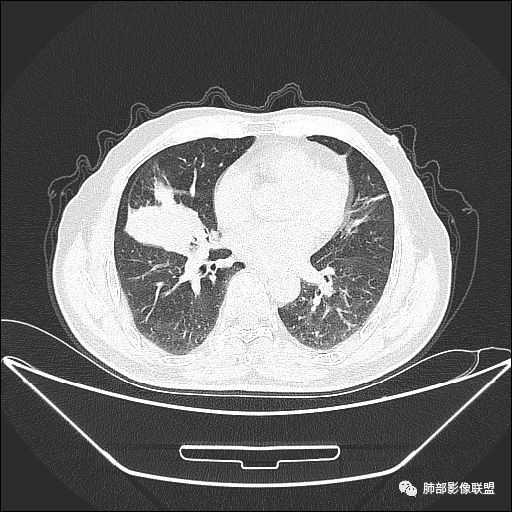

静脉期

老年男性,亚急性病程,咳嗽咳痰。右肺中叶团片影,外朝内分布,大部分边界清楚平直,内侧支气管进入,团片影见低密度坏死区,强化明显,延迟强化,血管破坏不明显,符合爬行征5个特点:

1.肺外周生长。

2.外侧部分体积大于内侧。

3.病变最大径与肺的纵轴及水平面任何一条轴线不平行。

4.病变内侧支气管通畅。

5.病变区域肺容积无缩小。

双侧肺门及纵隔淋巴肿大并可见钙化。考虑结核,但部分边缘膨隆,肿瘤待排。

主病灶在中叶,但是左肺舌段叶有条索影,陈旧病变。蓝色箭头支气管受压,是淋巴结肿大

主病灶在中叶,但是还有结节状病变在下叶

虽然是一个大的病灶,但是周围是比较散

这个支气管是走形通畅,但是壁增厚的。比较符合炎症改变

边缘还有多发小灶

淋巴结肿大,钙化。

病灶明显平直,中央是粘液栓,低密度,分界清楚

综上,考虑炎症,结核。